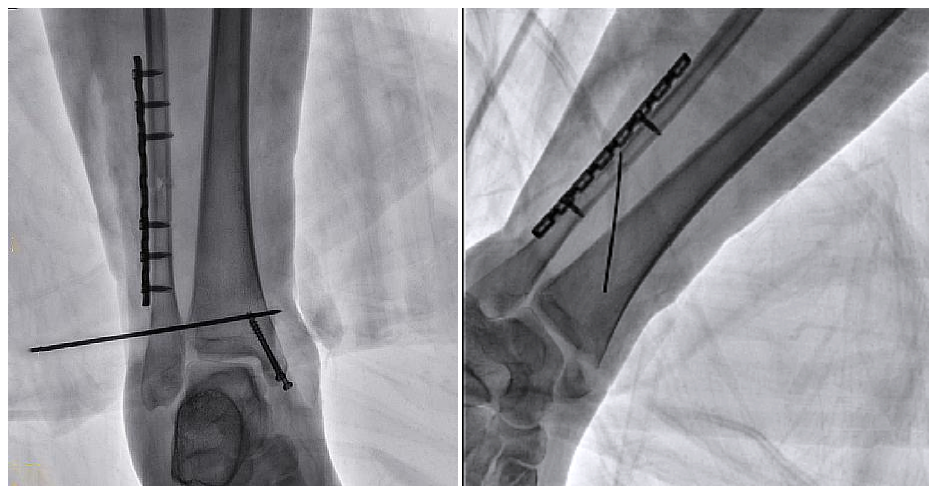

病例2 踝关节骨折复位(31岁)

在踝关节骨折复位手术中,用三维C可以更好地观察骨折部位的复位情况:

正侧位影像观察胫腓联合复位良好

从三维影像看,复位欠佳,贴合度不够

二维C形臂提供的影像存在固有局限性,其成像原理是基于单一方位的投影,导致深部解剖结构信息缺失,且容易受到骨骼和组织的重叠干扰,使得部分病灶难以清晰显示,甚至被掩盖。相比之下,三维C形臂通过三维重建技术,可以获得类似CT的断层扫描图像,从而解决了二维影像的重叠问题。

医生能够利用这些三维图像,更直观、更深入地分析病变,进行全方位观察,例如:精确评估骨折复位情况、清晰显示内植入物的位置及其与周围组织的关系等。尤其在复杂骨折、脊柱手术、呼吸介入等临床场景中,三维C形臂提供的详细信息对手术导航和疗效评估至关重要。